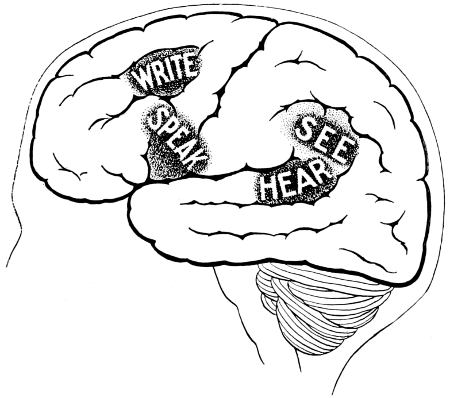

| 57. The areas concerned in speech expression | 163 |

Fig. 3. The Cortical Motor and Sensory Areas.

On the left side of the head—in normal right-handed individuals—the motor speech area of Broca corresponds to the third left frontal convolution, in the angle between the anterior and posterior horizontal limbs of the Sylvian fissure.

Finally, the four areas concerned in speech—motor speech, writing, reading, and hearing—are anatomically separated from one another and yet closely associated, so much so that one can hardly be involved without the other. The motor speech centre of Broca has already been mentioned as occupying—in right-handed individuals—the posterior part of the third left frontal convolution. Writing lies immediately above and in front, in the posterior part of the middle frontal gyrus, auditory impressions are received in the posterior and upper part of the first temporo-sphenoidal lobe, whilst the power of reading is dependent on the integrity of the supramarginal and angular gyri (see also Fig. 57).